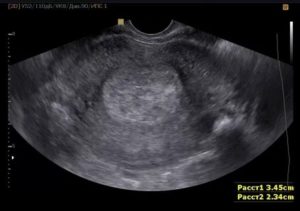

- Еще одно заболевание, симулирующее беременность — киста желтого тела.

Для уточнения факта наличия беременности, когда на УЗИ не видно плодного яйца, измеряется желтое тело, размеры которого будут выше нормы.

Кроме размеров шейки, с помощью УЗИ выявляют различные заболевания.

- Полип — доброкачественное разрастание слизистой. Располагается внутри цервикального канала, на снимке представлен серым округлым образованием.

- Рак — злокачественная опухоль. Растет внутри или снаружи цервикального канала. Представлена темно-серым или белым цветом, имеет неправильную форму.

Эндометриоз — разрастание слизистой матки за ее пределами. На снимке внутри цервикального канала определяются темные разрастания неправильной формы.